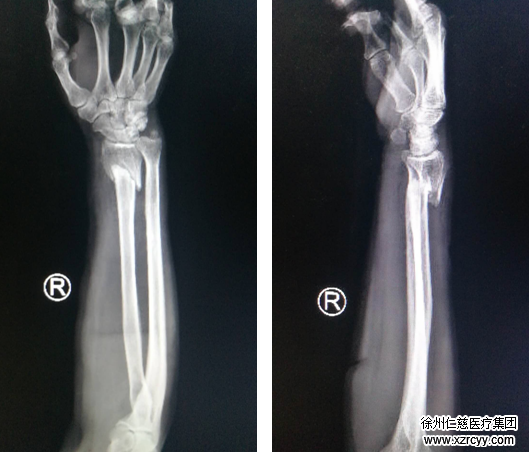

9月15日下午2点多钟,家住铜山区的王阿姨在工地干活时不慎被“铁管”砸伤右腕,当时手腕就变形了,又肿胀又痛,于是急忙赶来必威官方首页官网betway,一拍片子:桡骨远端骨折、尺骨茎突骨折。

经检查:王阿姨尺骨桡骨闭合性骨折。手外三病区吴尧医生随即对王阿姨实施桡骨骨折切开复位内固定术。在右腕桡掌侧作一长约1.5cm纵行切口,将一块T型锁定板平行置于右桡骨掌侧,依次钻孔、功丝、测深,8枚金属锁定螺钉依次拧入,手术非常顺利。